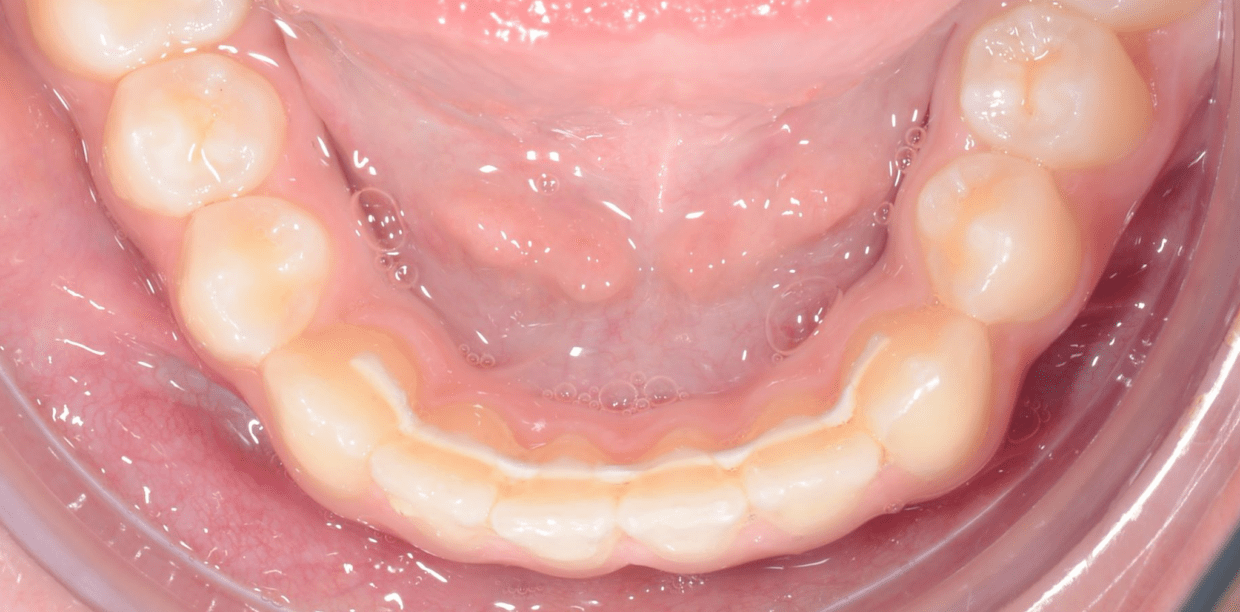

Cas cliniques

Simple - A2

Simple - A2

Simple - A2